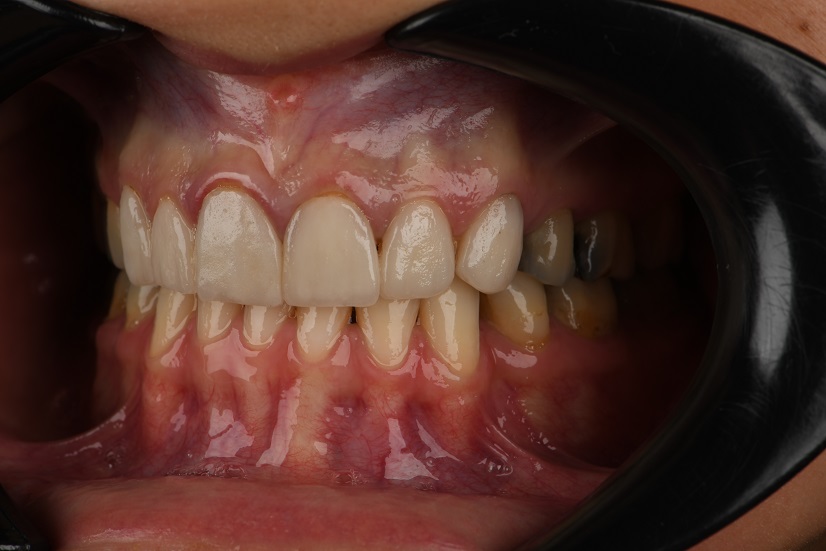

یکی از بیماران ما با لمینیت‌های قدیمی و فرسوده مراجعه کردند که ظاهر طبیعی و کیفیت اولیه خود را از دست داده بود. پس از مشاوره و بررسی دقیق، تصمیم به برداشتن لمینیت‌های قبلی و جایگزینی آن‌ها با 8 واحد لمینیت سرامیکی به رنگ طبیعی گرفتیم.

در ابتدا، لمینیت‌های قدیمی به دقت و بدون آسیب به دندان‌های طبیعی بیمار برداشته شد. سپس، با استفاده از تکنیک‌های پیشرفته و مواد باکیفیت، لمینیت‌های جدید طراحی و روی دندان‌های بیمار نصب شدند.

نتیجه نهایی دندان‌هایی با ظاهری زیبا، طبیعی و هماهنگ بود که رضایت کامل بیمار را به همراه داشت. این درمان نه تنها به بهبود ظاهر لبخند بیمار کمک کرد، بلکه استحکام و دوام بیشتری را برای دندان‌ها فراهم نمود.

بعد درمان